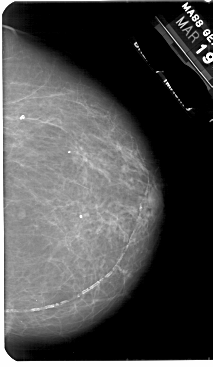

A_1836_1.LEFT_MLO

LEFT_MLO LINES 5491 PIXELS_PER_LINE 3481 BITS_PER_PIXEL 12 RESOLUTION 43.5 OVERLAY